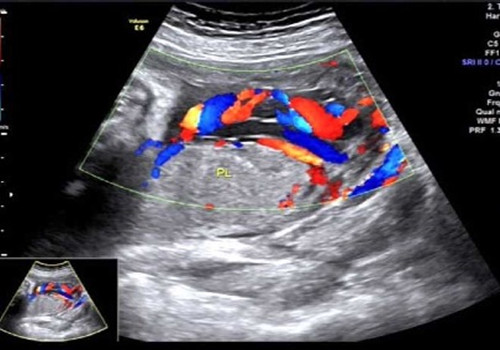

2017年7月10日上午就是在這間小黑屋里,一名34周孕婦正在進(jìn)行產(chǎn)科常規(guī)超聲檢查,當(dāng)探查到胎盤(pán)時(shí),朱新娟醫(yī)師一臉凝重,她發(fā)現(xiàn)了異常!經(jīng)科主任吳建軍、副主任醫(yī)師趙瑩會(huì)診,發(fā)現(xiàn)該孕婦腹中胎兒臍帶走形異常、并異常插入胎盤(pán),沿胎膜走行約5.2cm后才進(jìn)入胎盤(pán)實(shí)質(zhì),且血管聚集成堆于宮頸內(nèi)口處,考慮臍帶帆狀插入胎盤(pán)并血管前置。此現(xiàn)象是非常少見(jiàn)的產(chǎn)科急癥!極易造成血管斷裂!大出血!造成胎兒死亡!而這一切,產(chǎn)婦和家屬卻全然不知。情況緊急,朱新娟立即電話報(bào)告產(chǎn)科危急值!

聲像圖示:臍帶帆狀插入胎盤(pán)并血管前置

產(chǎn)科接到危急值報(bào)告后,即刻將該孕婦收治入院,給予密切監(jiān)護(hù)、治療,并于7月20日上午9:40,為該孕婦行剖宮產(chǎn),娩出一名2000g女?huà)?,母女平安!?shù)十分鐘后胎盤(pán)娩出,確系少見(jiàn)的臍帶帆狀插入胎盤(pán)并血管前置!產(chǎn)科馬主任激動(dòng)地拉著吳主任的手說(shuō):“你們超聲醫(yī)生太棒啦!你們就是我們產(chǎn)科醫(yī)生的眼睛!不但救了這對(duì)母女,也‘救’了我們產(chǎn)科醫(yī)生??!”